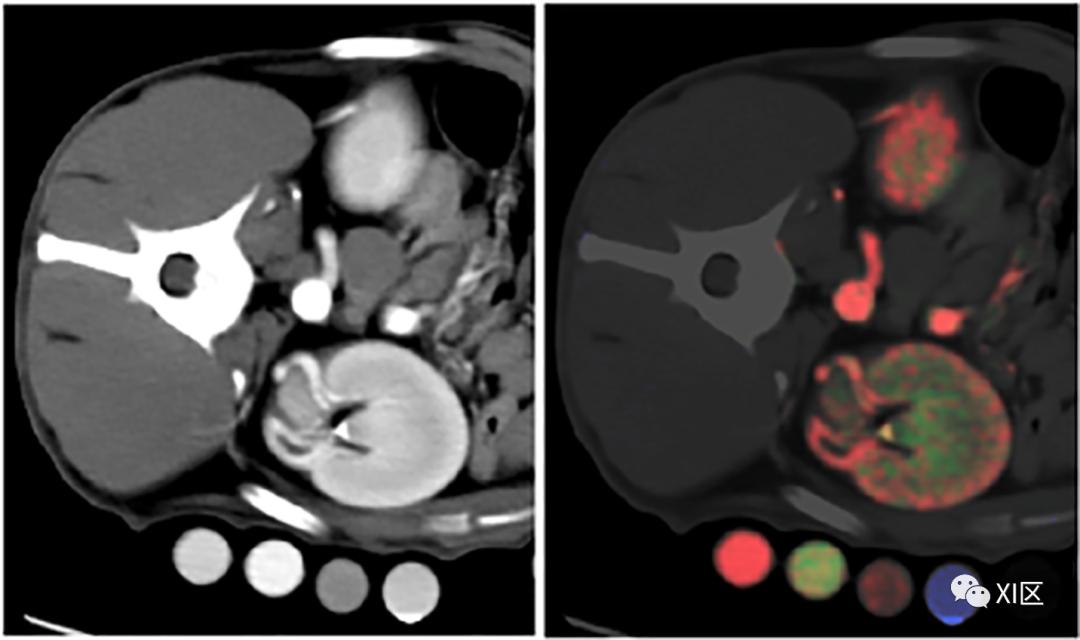

图14 67岁女性患有肾上腺腺瘤和肾盂旁肾囊肿的腹部图像,采用带有光子计数探测器的临床前单源CT原型采集。数据采集:“标准”模式,144x0.4 mm准直,0.3 s旋转时间,CTDIvol=10.2 mGy,DLP=450 mGy·cm。图像重建:VMI为190 keV,65 keV,55 keV和45 keV,0.4 mm层厚。请注意,随着keV的增加,碘和钙的对比度降低-190 keV图像可以替代虚拟平扫图像。一些作者评估了光谱光子计数CT在肾结石检测和特征描述方面的性能。他们发现,在鉴别结石成分方面,整体表现与最先进的双能CT相当,而光子计数CT能够更好地帮助确定小肾结石的特征。